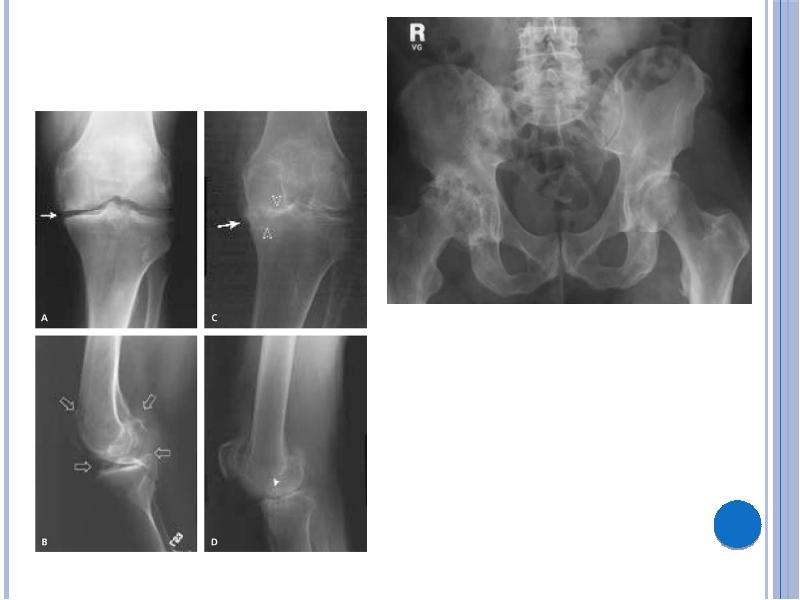

На рентгенограммах тазобедренный сустав сохраняет нормальную форму, суставная щель умеренно или неравномерно сужена с субхондральным склерозированием костных суставных поверхностей, непостоянными краевыми костными разрастаниями (I стадия).

Рентгенологически суставная щель может быть равномерно или неравномерно сужена, ацетабулярная суставная впадина уплощена, присутствуют явления субхондрального склероза, краевые костные разрастания. Конфигурация головки бедренной кости, как правило, не нарушена (II стадия).

В подавляющем большинстве случаев диагноз коксартроза ставится при рентгенографии, где видны изменения формы и структуры костей, составляющих тазобедренный сустав. Однако рентгенографически в ряде случаев затруднительно зафиксировать ранние проявления артроза, так как хрящевая ткань суставных поверхностей на рентгеновских снимках не отображается и мы можем судить о дегенеративном процессе, когда он достаточно выражен, вызывая изменения ширины просвета рентгеновской суставной щели.

КТ тазобедренного сустава проведено с 2002 года в 80, МРТ с 2011 года — в 22 случаях. Предпочтение следует отдать МРТ, так как при данном виде исследования можно четко визуализировать суставную капсулу и связки, идентифицировать даже поверхностные изменения хрящевого слоя, а также мелкие очаги субкортикального трабекулярного отека губчатого вещества костной ткани. КТ позволяет оценить минимальные изменения структуры и формы костной ткани, однако в общем объеме получаемой информации уступая МРТ в информативности. При углубленном обследовании для уточнения диагноза «коксартроз» и степени его выраженности можно рекомендовать проведение именно МРТ тазобедренных суставов.

На ранних стадиях диагностировать артроз можно только при проведении КТ или МРТ.

Выводы. Таким образом, учитывая доступность и экономическую целесообразность, скрининговыми методами диагностики коксартроза являются рентгенография и УЗИ тазобедренных суставов. При несоответствии клинической картины и данных методов исследования необходимо КТ и (или) МРТ, что позволяет повысить качество диагностики и назначить адекватную терапию.